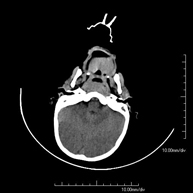

- Neurorradiología

- TC Cráneo

Prueba radiológica que consiste en obtener imágenes del cráneo de alta definición anatómica (tronco cerebral, cerebelo, cerebro, calota craneal, etc.), mediante el empleo de un equipo de TC (Tomografía Computarizada).Indicaciones: traumatismos, cefalea, trastornos de la memoria, pérdida de fuerza súbita en una extremidad o mitad del cuerpo.